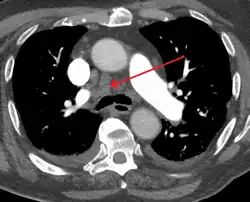

Mediastinal adenopathy

The mediastinum is frequently the site of involvement of various tumors:

• Middle mediastinum: lymphadenopathy, metastatic disease such as from small cell carcinoma from the lung.